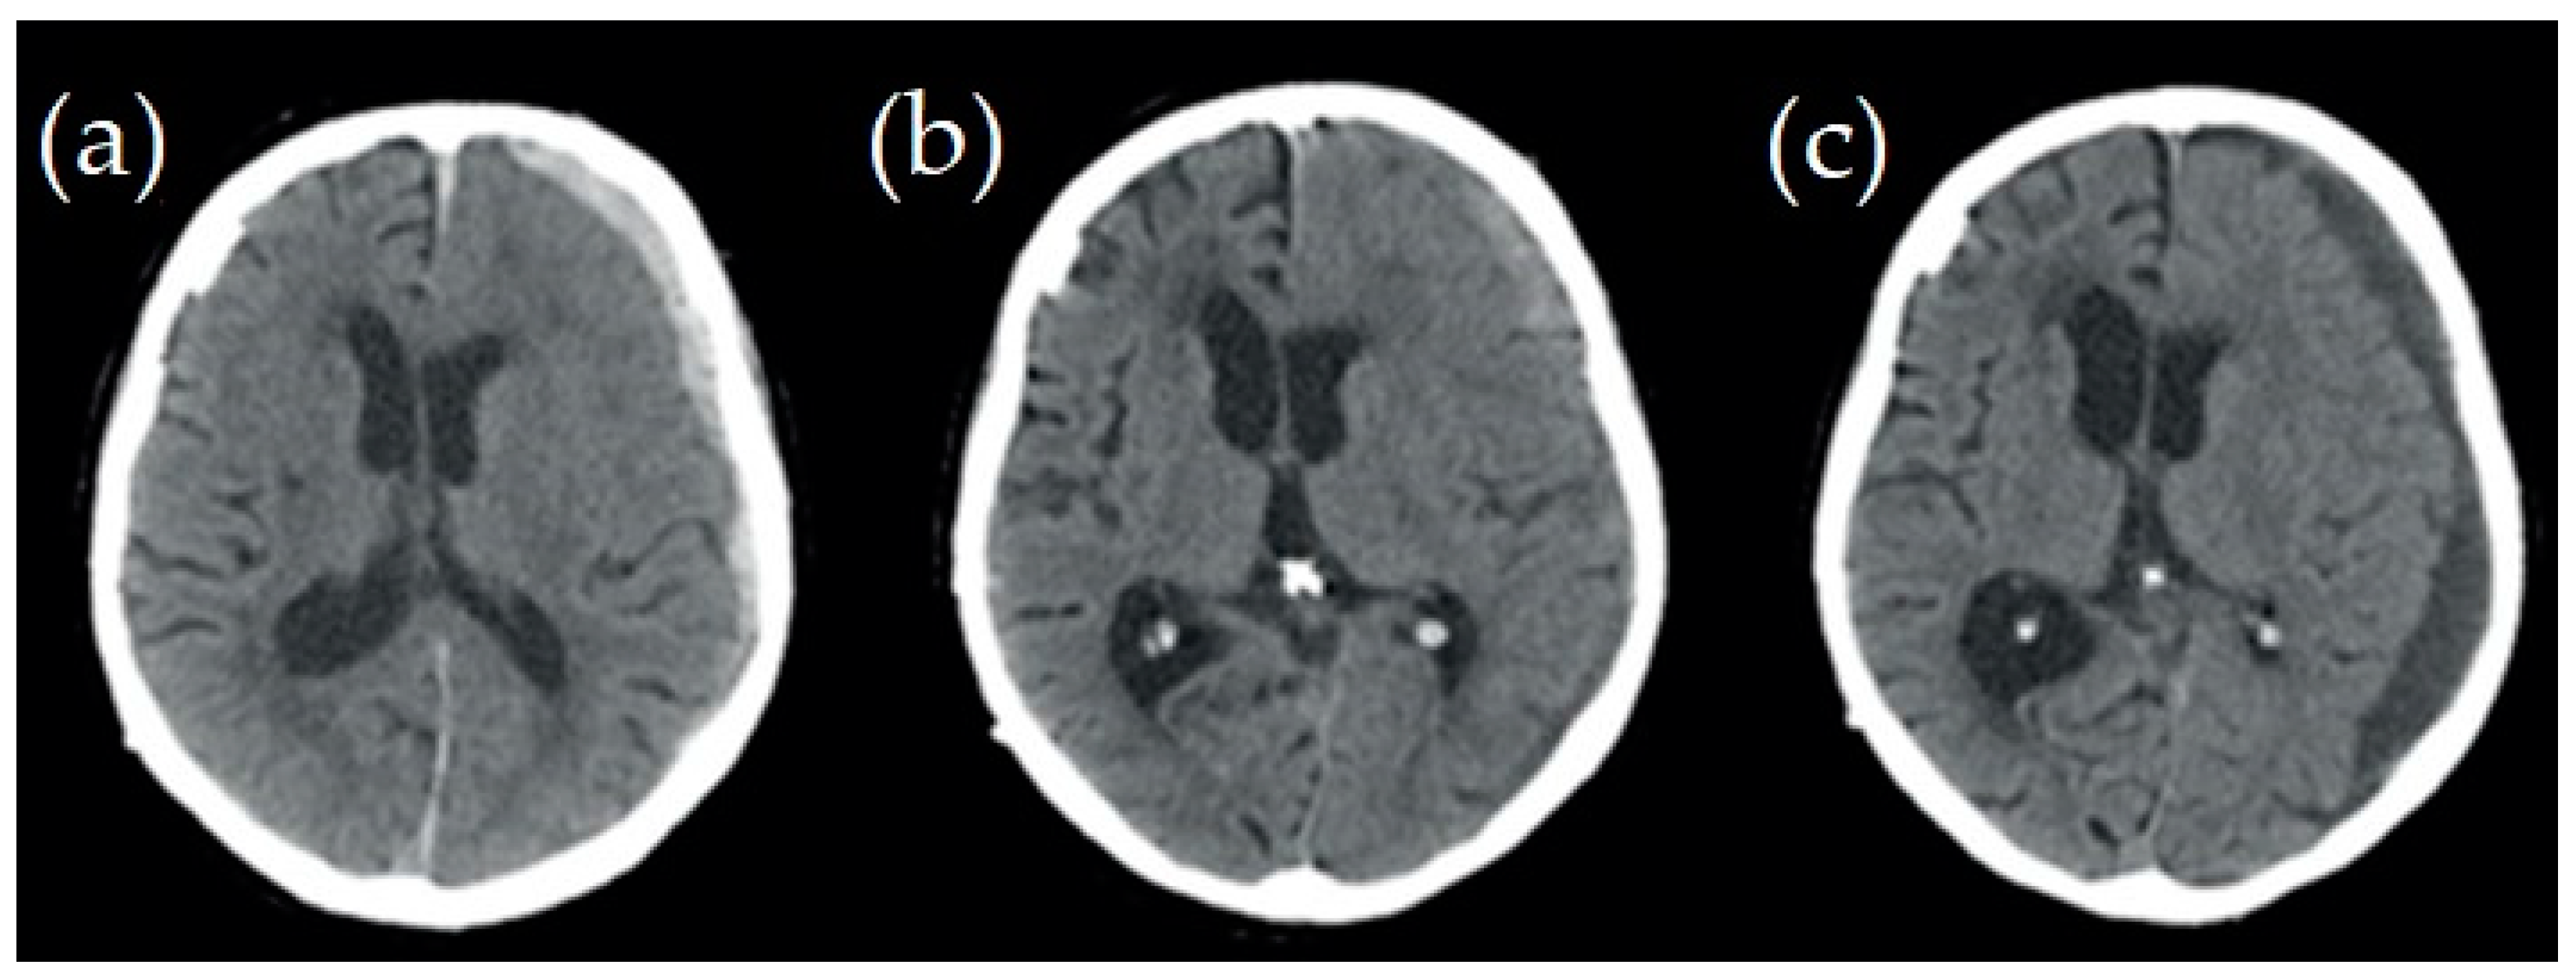

2.1. Case Studies